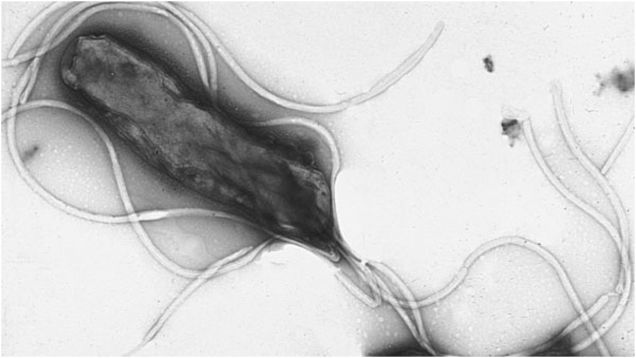

A common bacterial infection that causes stomach ulcers and cancer has gotten increasingly harder to fend off, according to new preliminary research out this week. In Europe, it suggests, strains of the bacteria Helicobacter pylori have become more resistant to the first-line drugs used to kill it over the past 20…

Source: Gizmodo – The Bacteria That Cause Stomach Ulcers Are Becoming Drug-Resistant, Too